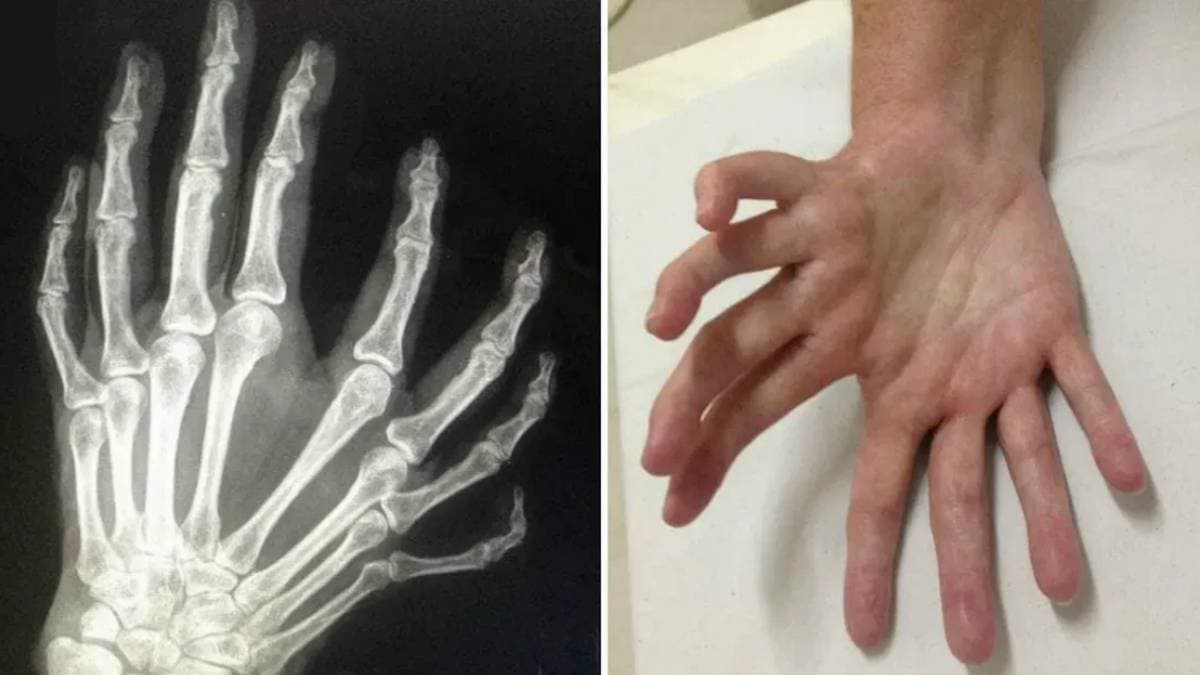

হাতের আঙুল না মাকড়সার পা? ধরতে পারবেন না! বিরল এই আট আঙুলের হাত দেখে চমকে ওঠেন চিকিৎসকেরাও